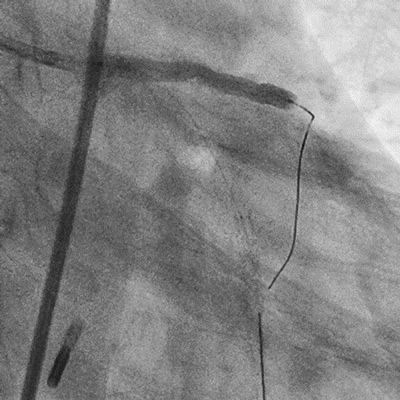

We decided to use rotablation for calcified plaque modification (extra-support wire, 1.5mm burr)

Speed of 180 000 rpm

As soon as the lesion was crossed, the rota burr got stuck in the lesion

Guideliner 5Fr to remove the rota burr (cut off the drive shaft and sheath) but the tip was too flexible

Solution No.4

ST-01 mother-and-child catheter inserted and the rota burr removed successfully